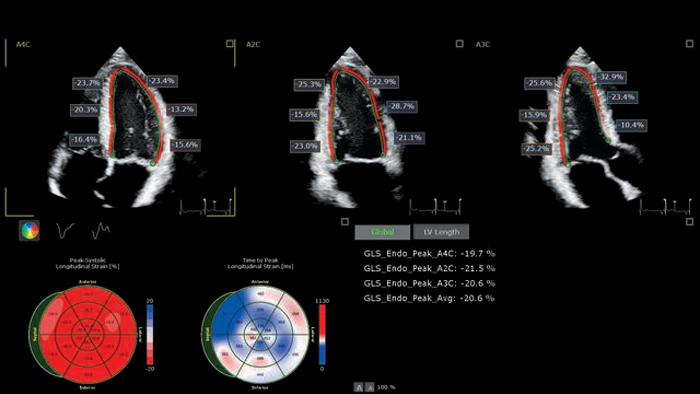

The EPIQ CVx is a dedicated cardiac ultrasound solution which brings significant advancements in functionality. This helps you deliver better care through higher processing power, exceptional imaging with more clarity & sharpness, improved exam efficiencies, complemented by the proven, robust quantification capabilities of Ultrasound Workspace.

Streamline echocardiography workflow across your organization with Philips Ultrasound Workspace. Built on the legacy of the TOMTEC ARENA platform, it allows for greater efficiency in viewing, analysis and reporting by giving care teams the flexibility to adopt different workflows based on their current and future needs.